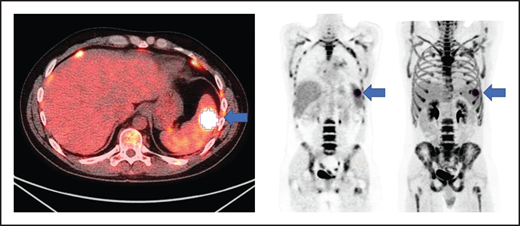

MTV measurement

All patients had baseline 18F-FDG PET/CT scans before lymphodepletion and CD30.CAR-T cell infusion. In patients who had a 18F-FDG PET/CT prior to bridging therapy, these scans were evaluated for MTV to provide a tumor burden comparison before and after bridging therapy. 18F-FDG PET/CT scans were evaluated using MIM 7.0.5 (MIM Software, Cleveland, OH). MTV was computed using the threshold tool in MIM with a threshold 41% of the maximum standardized uptake value (SUV), or SUVmax, as described elsewhere.10-14 The lesion was manually selected and the region of interest increased until all voxels at least 41% of the SUVmax (Figure 1). MTV for each patient was determined by summing the volumes of lesions with voxels at least 41% of the SUVmax.

Axial fused, coronal PET-only, and maximum intensity projection images. Representative lesion segmented using 41% of SUVmax as cutoff (blue arrows).

Axial fused, coronal PET-only, and maximum intensity projection images. Representative lesion segmented using 41% of SUVmax as cutoff (blue arrows).